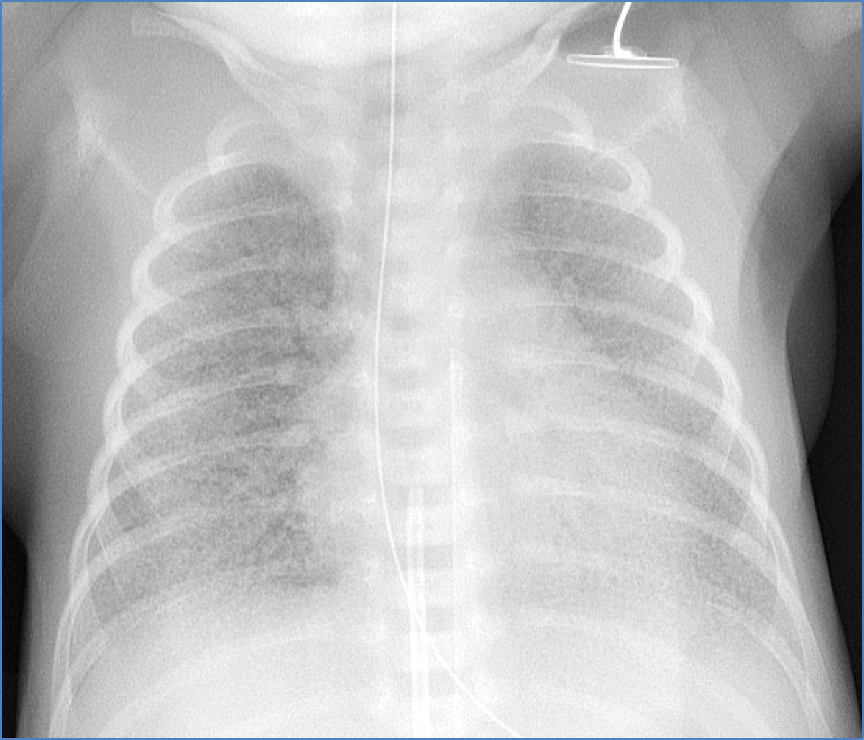

- CXR: patchy infiltrates, hyperinflation, flattened diaphragm